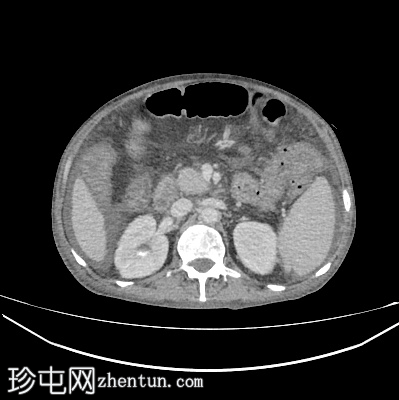

轴位

平扫

肝脏轻度肿大,未见肝内胆管扩张。近端和中段胆总管扩张至8 mm,远端突然中断,门周脂肪间隙增厚。

胰腺轻度肿大,胰周脂肪间隙增厚,符合急性胰腺炎表现。

胃大弯壁内可见一囊肿,大小为7.6 × 4.3 cm,囊壁厚度为2.5 mm,可见强化。脾门处可见另一囊肿,大小为 4.8 × 3.0 cm。

盲肠和升结肠壁水肿增厚,可能为反应性改变。

腹主动脉、脾动脉、腹腔干和肠系膜上动脉可见动脉粥样硬化改变。

中度腹水。双侧轻度胸腔积液(右侧较左侧多)。